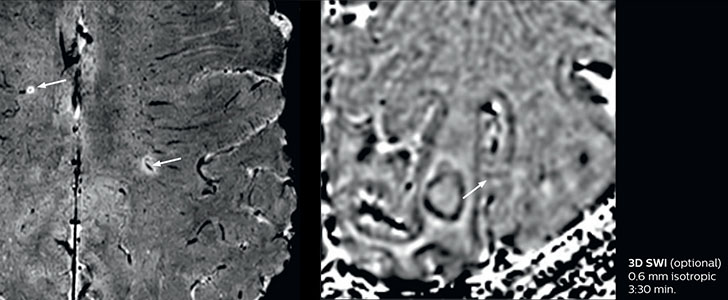

The abbreviated MS protocol for brain is only around 9 minutes, so in case of suspected multiple sclerosis, one or two more advanced sequences may be added, such as PSIR (phase sensitive inversion recovery) or susceptibility-weighted sequences to help us make more confident diagnoses in these inflammatory cases.

In this example, the optional 3D multishot susceptibility weighted sequence with 0.6 mm isotropic voxels is 2 lesions with a central vein sign (arrows) and one lesion with a phase-rim sign (arrowhead). The total scan time, including SmartBrain and axial PD/T2 3mm, is 11:10 min. and is 18:30 min. with the optional 3D PSIR and 3D SWI multishot included.

“In multiple sclerosis patients, we increasingly include a multishot susceptibility sequence [3] in our routine cases, thanks to the shorter scan times. Our abbreviated MS protocol for brain is around 8 to 9 minutes, so we can ask for one or two additional sequences to visualize the central veins, or to get an additional contrast to better depict posterior fossa lesions. In cases of white matter lesions of unknown significance on FLAIR images, for example when we see high signal hyperintensities in the brain, we can add on more advanced sequences such as PSIR (phase sensitive inversion recovery) or susceptibility-weighted sequences to help us in distinguishing between MS and nonspecific or vascular abnormalities in these inflammatory cases.”